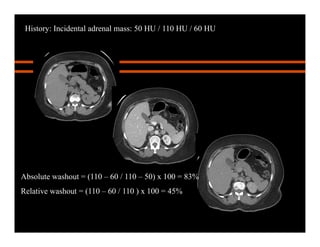

Absolute washout = (110 – 60 / 110 – 50) x 100 = 83%

Relative washout = (110 – 60 / 110 ) x 100 = 45%

Adenoma: APW, RPW

History: Incidental adrenal mass: 50 HU / 110 HU / 60 HU